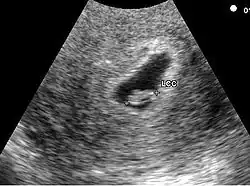

L'aspect échographique du tout début de grossesse

• Le premier signe échographique d'une grossesse est la visualisation d'un sac ovulaire. Il est visible entre 4 semaines et 1 jour et 4 semaines et 3 jours; Il mesure alors 2 à mm. L'utilisation de la voie endovaginale est souvent nécessaire pour le voir. Le sac ovulaire a l'aspect d'une petite tache noire, excentrée par rapport à la cavité utérine, correspondant à la cavité chorionique entourée d'une couronne d'échogénéicité forte : le trophoblaste.

• À cinq semaines, le sac ovulaire mesure mm. Il est quasiment toujours visible lors de l'échographie par voie abdominale. Il est parfois difficile d'affirmer la localisation intra-utérine de la grossesse en raison de l'aspect de pseudo-sac gestationnel décrit au cours des grossesses extra-utérines. Seuls deux signes sont pathognomoniques de la grossesse intra-utérine

• L'aspect en double cercle du sac (double decidual sac sign) correspondant une couronne hyper-échogène interne en rapport avec la trophoblaste et une couronne hypo-échogène externe en rapport avec la transformation gravidique de l'endomètre

• La visualisation de la vésicule vitelline qui affirme définitivement le caractère ovulaire de l'image échographique.

• La visualisation de la vésicule vitelline est un élément essentiel pour affirmer le caractère ovulaire de l'image et l'évolutivité de la grossesse. Embryologiquement, la vésicule vitelline visualisée correspond à la seconde vésicule vitelline. La vésicule vitelline est toujours visible à 5 semaines et 5 jours par voie endovaginale. Le sac ovulaire mesure en moyenne mm. Par voie abdominale, elle est toujours visible à 7 semaines (le sac ovulaire mesure en moyenne 20 mm). Le diamètre de la vésicule vitelline augmente de 5 à 10 semaines pour atteindre 5 à mm.